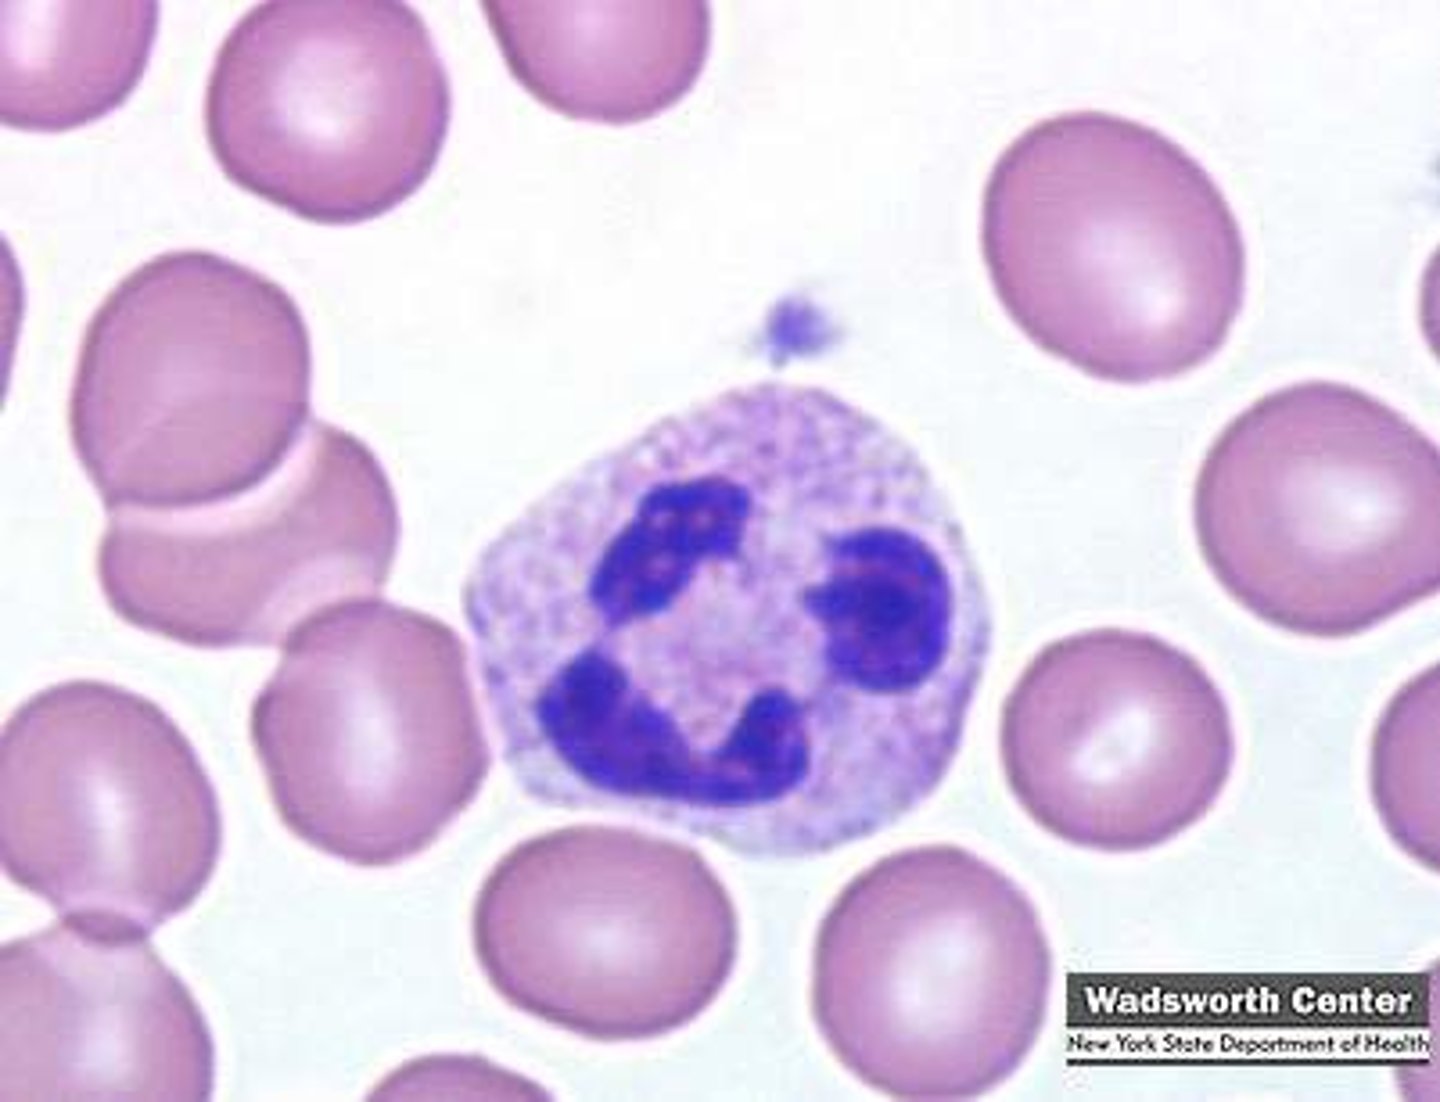

Blood

What is this?

Abnormal

Is this blood slide normal or abnormal?

Neutrophil

what is this?

lymphocyte

what is this?

Macrophage

what is this?

Eosinophil

what is this?

monocyte

what is this?

basophil

what is this?

platelet

what is this?

Red Blood Cell

what is this?